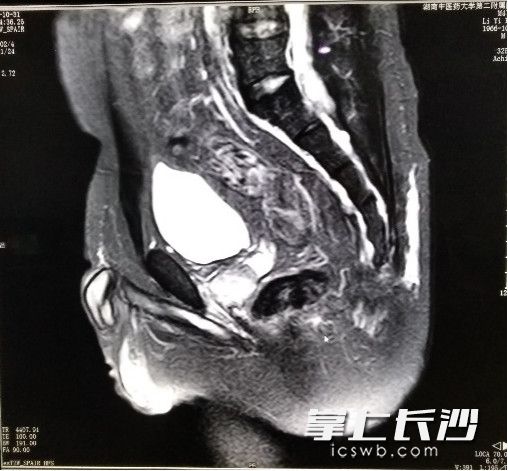

患者术后复查的核磁共振检查片。

该科何永恒教授、谢彪主任建议全院各相关科室专家进行会诊。专家讨论后一致认为,虽然手术风险大,患者仍有手术根治的机会,经讨论专家为患者制定了周全的手术方案和应急预案。在脊柱外科刘晓岚主任的紧密协作下,手术顺利进行。幸运的是,切除尾骨后,患者不仅囊肿和肿瘤得以彻底切除,直肠没有受到损伤,因此无需进行造瘘术,患者术后进行了病理检查,结果为良性畸胎瘤。经过10余天的后续治疗,患者于今日顺利出院。